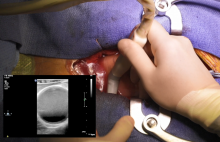

Epiaortic scanning is a simple and low-cost technique that could improve results in terms of postoperative neurological complications. This video is a step-by-step tutorial that could allow every surgeon to perform an epiaortic scan safely. The findings from the scan may help in choosing the optimal surgical strategy for every single patient. The authors show how to set up the probe, the different views, and how to analyze the findings.